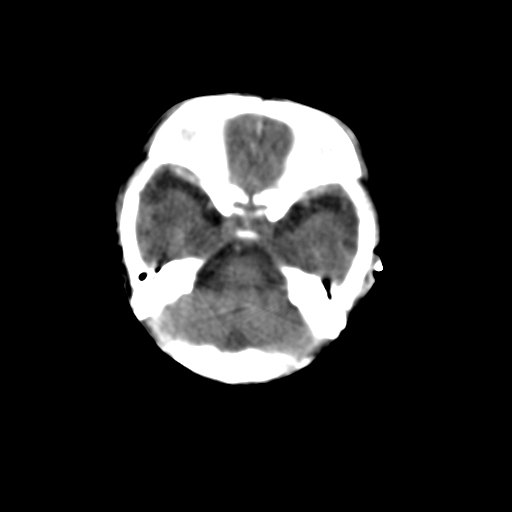

新生儿女2天,有窒息史,经抢救好转!白质最低ct值>23hu,请教各位老师:是否有出血?是否合并缺氧脑病?谢谢!

hie、蛛网膜下腔出血,皮下血舯。

hie、蛛网膜下腔出血,皮下血舯。透明隔间腔形成支持

空三角征,蛛网膜下腔出血。